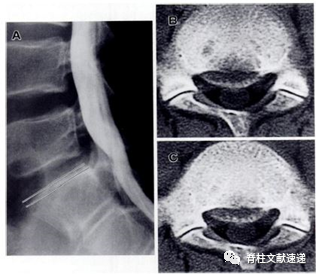

Takata等将椎体后缘离断症分为三型:I型,椎体后皮质缘单纯离断;Ⅱ型,椎体后缘含松质骨离断;Ⅲ型,椎体后缘局部离断。Ⅱ型是椎体后缘的撕脱骨折,包括纤维环上覆的软骨。与I型骨折相比,碎片较厚,可见与骨碎片相对应的骨缺损。

Takata分型:I、Ⅱ、Ⅲ型示意图三种类型骨折的图示。在I型中可见弧形碎片,但椎体后缘未见骨缺损。Ⅱ型是椎体后缘的撕脱骨折,碎片不是弧形的,CT横断位可以识别出骨质边缘尖锐撕脱。Ⅲ型是椎体后缘不规则后的局部离断。

I型(A)、Ⅱ型(B)、Ⅲ型(C型)、Ⅳ型(D-G)